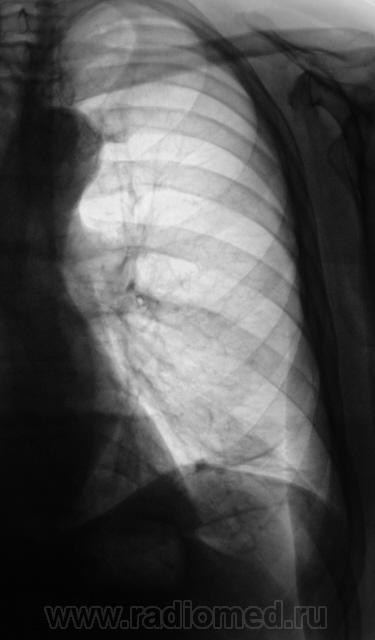

Легкие без очаговых и инфильтративных изменений, увеличены в объеме и прозрачности (эмфизема). Особенно увеличен объем язычковых сегментов левого легкого, несколько уменьшена в объеме нижняя доля. Левый купол диафрагмы расположен несколько выше нормы, особенно задние отделы, плевро-диафрагмальная спайка, увеличено расстояние до газового пузыря желудка. Предварительное заключение: подозрение на нарушение бронхиальной проходимости в левом легком, базальный гидроторакс слева. Дообследование: линейная томография (боковая проекция обязательна, может быть очень информативной), латерография для исключения/подтверждения свободной жидкости в левой плевральной полости.

Легкие без видимых очаговых и инфильтративных измнений. По прямой рентгенограмме левая половина диафрагмы расположена выше обычного. Прозрачность левого легочного поля выше правого. При изучении левой боковой рентгенограммы нижняя доля левого легкого резко уменьшена в объеме в пределах анатомических границ. Затенение базальных отделов левого легочного поля на фоне которого не дифференцируется левая половина диафрагмы. Викарная эмфизема верхней доли левого легкого.

Заключение(вывод): больше данных за ателектаз нижней доли левого легкого (гиповентиляция). Необходимо дополнительное исследование проходимости бронхиального дерева левого легкого. Бронхоскопия, ТМГ, КТ.

Слева в нижних отделах пневмофиброз, приподнятость диафрагмы, асимметрия грудных мышц или молочных желез - возможно было лучевое лечение опухоли левой молочной железы??? Если нет - Узи живота, бронхоскопия.

СЛЕВА ЗА 6 РЕБРОМ  ЛАТЕРАЛЬНО

ВРОДЕ БЫ ИМЕЕТСЯ  НЕБ. УЧАСТОК  УПЛОТНЕНИЯ ( НА  БОКОВОМ НЕ НАХОЖУ, ГДЕ).

СЛЕВА НАД  ДИАФРАГМОЙ  ЕДИНИЧНЫЕ  ЛИНЕЙНЫЕ  ШВАРТЫ,

ЗАДНИЙ СИНУС  ОБЛИТЕРИРОВАН, ЛЕВ.  КУПОЛ ДИАФРАГМЫ ПРИПОДНЯТ.

ФИКСИРОВАН  ПЛЕВРО-ДИАФР. СПАЙКАМИ. ХОРОШО БЫ ЗНАТЬ АНАМНЕЗ - ЧТО И КОГДА  БЫЛО СЛЕВА?

Ателектаз нижней доли левого л1гкого.

Что-то на ателектаз не похоже. Какие-то плевральные штучки.